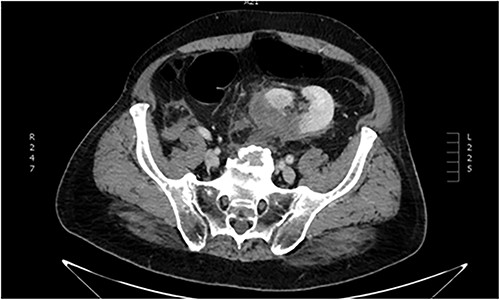

Imaging investigation with thoracic x-ray revealed 9th to 11th posterior rib fractures, as well as small pneumothorax on the right rib cage. Abdominal ultrasound revealed no internal bleeding or fluid within the peritoneal cavity and spaces, but an injured ectopic left kidney was detected within the pelvic cavity, previously unbeknownst to the patient. Further imaging with abdominal and pelvic computed tomography (CT) scan confirmed the occurrence of a grade III laceration (according to the American Association of the Surgery of Trauma—AAST renal injury grading scale) of the ectopic kidney (Figs. 1 and 2).

Abdominal CT imaging. Absence of left kidney from its usual anatomic position.